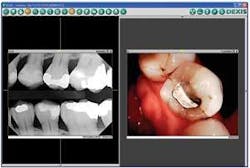

Whether you have a moderately priced or high-end intraoral or digital still camera, you and your team should take time to integrate it into your routine work flow. Make it a habit to capture camera images like you do X-rays. Just as an enlarged digital X-ray gets your patients’ attention and lets them see their condition, so do camera images.

After you’ve captured pictures, what do you do with the images? Don’t keep them to yourself! We show them on a 42-inch monitor that swings out from the wall to face the chair. You can do the same - show patients the images on your computer monitor.

These visuals are especially important with new patients with whom you haven’t had time to build solid relationships. When faced with the evidence of X-ray and camera images, patients feel sure you are suggesting treatment they really need. There’s no second-guessing your recommendation - patients essentially diagnose themselves!